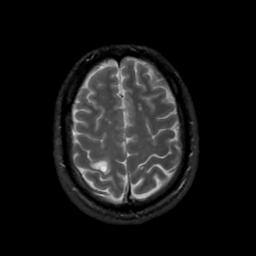

MR Study #4, March 3, 1991 -- Slice #40